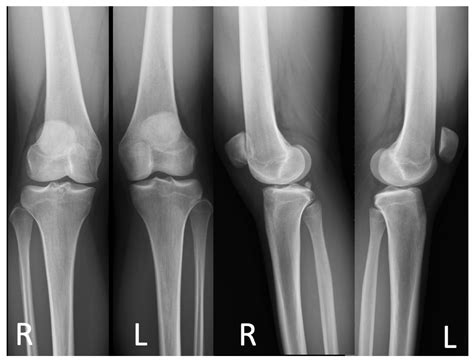

Experiencing knee pain, especially around the kneecap, can significantly hinder your daily activities, from climbing stairs to simply standing up after a long period of sitting. One common, yet frequently misunderstood, culprit behind this discomfort is lateral patellar tilt. This condition occurs when the patella (kneecap) drifts or rotates outward toward the outer side of the leg rather than sliding smoothly in its designated groove. Understanding what this is, why it happens, and how to manage it is crucial for anyone looking to restore pain-free movement and maintain long-term joint health.

The patella is designed to glide vertically within the femoral groove (the trochlear groove) of the femur. When the mechanics of the knee are balanced, this movement is seamless. However, lateral patellar tilt happens when the soft tissues—specifically the lateral retinaculum on the outside of the knee—become too tight, while the muscles on the inside are relatively weak. This imbalance causes the kneecap to tip outward, increasing pressure on the lateral facet of the patella. Over time, this abnormal tracking can lead to cartilage wear, inflammation, and chronic pain, a condition often categorized under patellofemoral pain syndrome (PFPS).